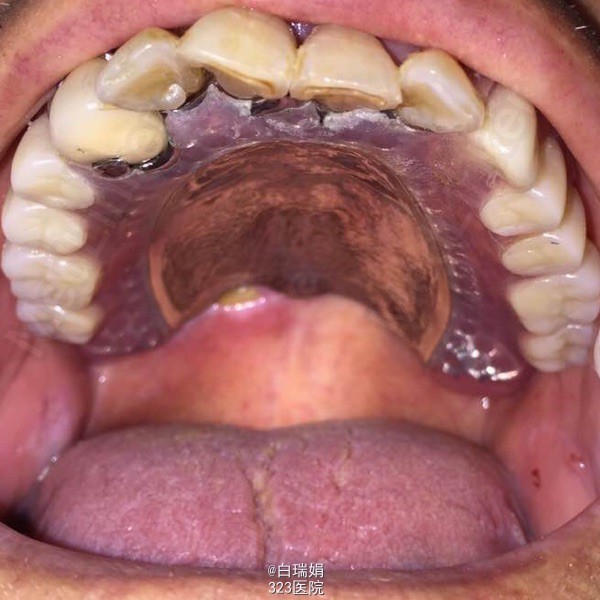

患者,男,78岁。 主诉:左上后牙疼痛不适一月余。 现病史:患者述五年前左上后牙行烤瓷冠修复,近半年来自觉松动,咬物疼痛不适,近一个月症状加重,未做处理,现前来要求检查治疗。既往体健,无全身系统疾病时,药物过敏史及传染病史。

检查:左上3至左上7烤瓷联冠,松动2度,左上3、4、5、7叩诊(➕),左上7腭侧牙根吸收至根中1/3,右上4至右上7缺失,缺牙区牙槽嵴尚可,无明显骨突骨刺;X线示左上3、4、5牙周膜间隙增宽,根尖区低密度影像,左上5远中牙槽骨吸收至根中1/3,左上7牙槽骨吸收至根尖。

诊断:1、牙列缺损 2、左上烤瓷冠桥松动 3、左上3、4慢性根尖周炎 处理:1、拆除左上烤瓷冠桥,拔除左上5、7 2、左上3、4截冠后常规行根管治疗 3、左上3治疗后无症状制作根面磁性附着体 4、粘接根面附着体后取上下颌模型,纪录咬合关系,制作活动义齿 5、试戴蜡型,调整咬合关系,戴活动义齿,调合抛光,粘接另一半磁铁